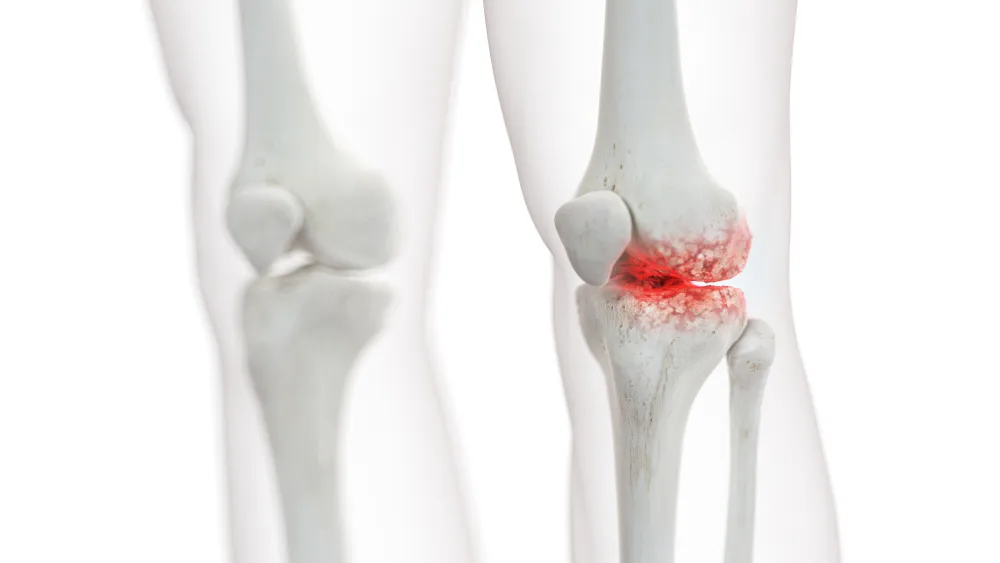

Joint Preservation Procedures

Joint preservation procedures are advanced medical and surgical techniques aimed at maintaining the natural joint structure, function, and mobility, thereby delaying or avoiding the need for joint replacement. These procedures...